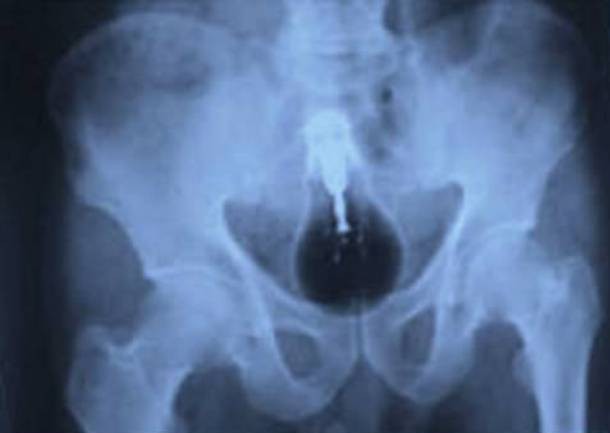

10. Bóng đèn trong... xương chậu tù nhân...

Trường hợp này xảy ra tại một trại giam ở Pakistan, và mặc cho bác sĩ cạy miệng, thanh niên tù nhân này vẫn không hé răng nửa lời về việc tại sao chiếc bóng đèn này lại nằm ở đây.